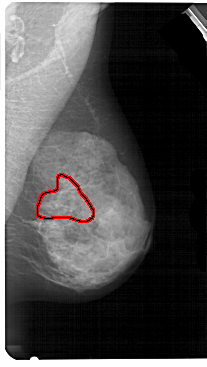

A_1605_1.LEFT_MLO

LEFT_MLO LINES 5281 PIXELS_PER_LINE 3211 BITS_PER_PIXEL 12 RESOLUTION 43.5 OVERLAY

FILE: A_1605_1.LEFT_MLO.OVERLAY

TOTAL_ABNORMALITIES 1

ABNORMALITY 1

LESION_TYPE CALCIFICATION TYPE PLEOMORPHIC DISTRIBUTION SEGMENTAL

ASSESSMENT 4

SUBTLETY 3

PATHOLOGY BENIGN

TOTAL_OUTLINES 1

BOUNDARY